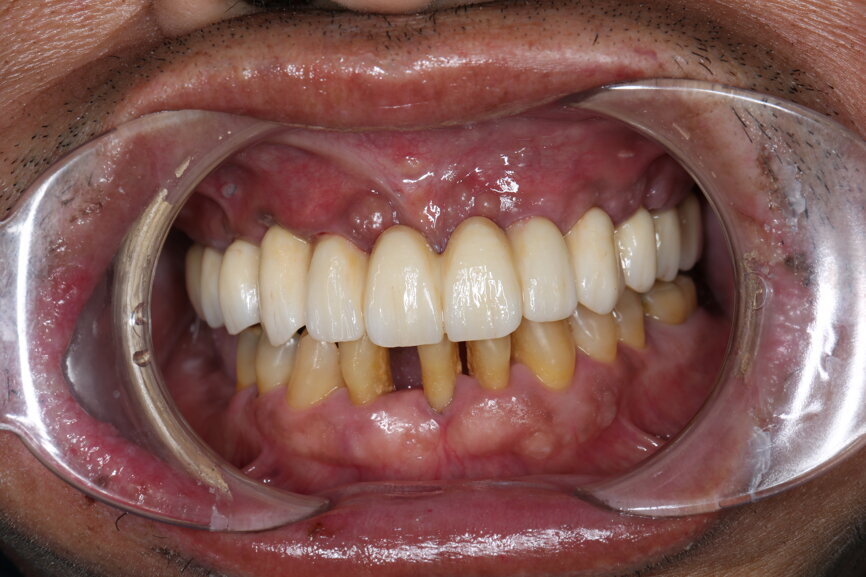

Five-day follow-up

After five days, the patient returned to the clinic, and the PMMA temporary restoration was removed and the zirconia temporary restoration was placed, allowing a passive fit on the abutments with initial hand tightening of each SRA up to 5 Ncm. After the seating had been checked, the torque of each SRA screw was increased up to 35 Ncm, and the restoration was screwed in at a torque of 15 Ncm. The occlusion was checked, and the contacts were inspected. The screw holes were sealed with PTFE and a temporary filling material (Fig. 65). A panoramic radiograph was taken, and the SRA screw positions were evaluated to confirm the perfect fit of the temporary restoration (Fig. 66). Oral hygiene and dietary instructions were given to the patient, and a one-week follow-up appointment was scheduled.